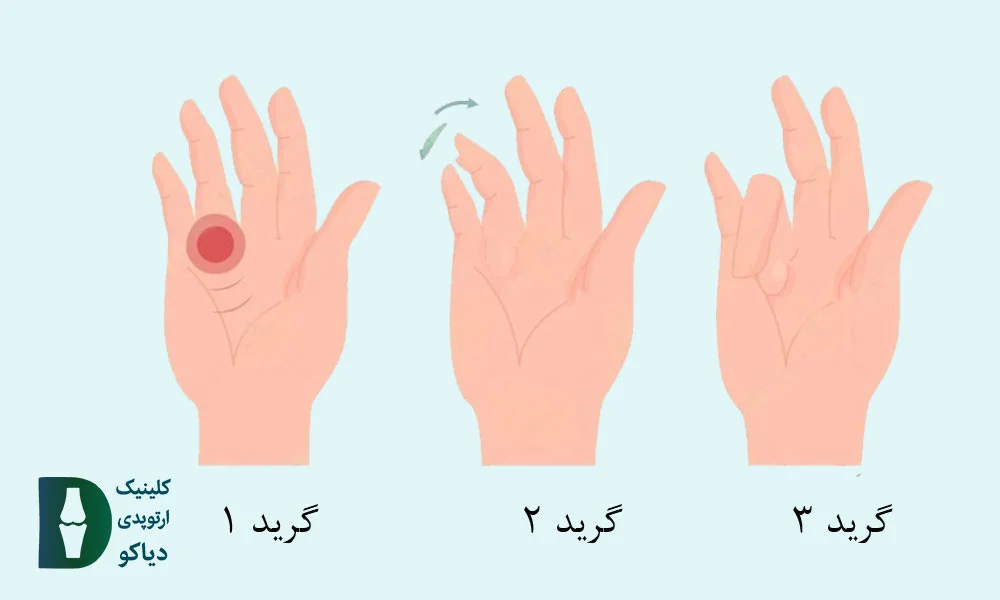

درجهبندی شدت انگشت ماشهای (Green Classification):

برای ارزیابی شدت انگشت ماشهای، از سیستم درجهبندی Green استفاده میشود. این دستهبندی، بر اساس میزان قفلشدگی انگشت و توانایی فرد در خم یا صافکردن آن طراحی شده و راهنمای مناسبی برای انتخاب روش درمانی است (منبع).

در ادامه، انواع گریدها را بررسی میکنیم.

درد و حساسیت در کف دست بدون مشاهده قفلشدگی در معاینه. |

انگشت هنگام حرکت قفل میکند اما بیمار قادر به صافکردن فعال آن است. |

انگشت در حالت خمشده قفل میماند و برای صافشدن نیاز به کمک دست دیگر دارد. |

انگشت قفلشده است و بیمار قادر به خمکردن فعال آن نیست. |

انگشت در وضعیت خم باقی مانده و دچار محدودیت دائمی حرکت شده است. |